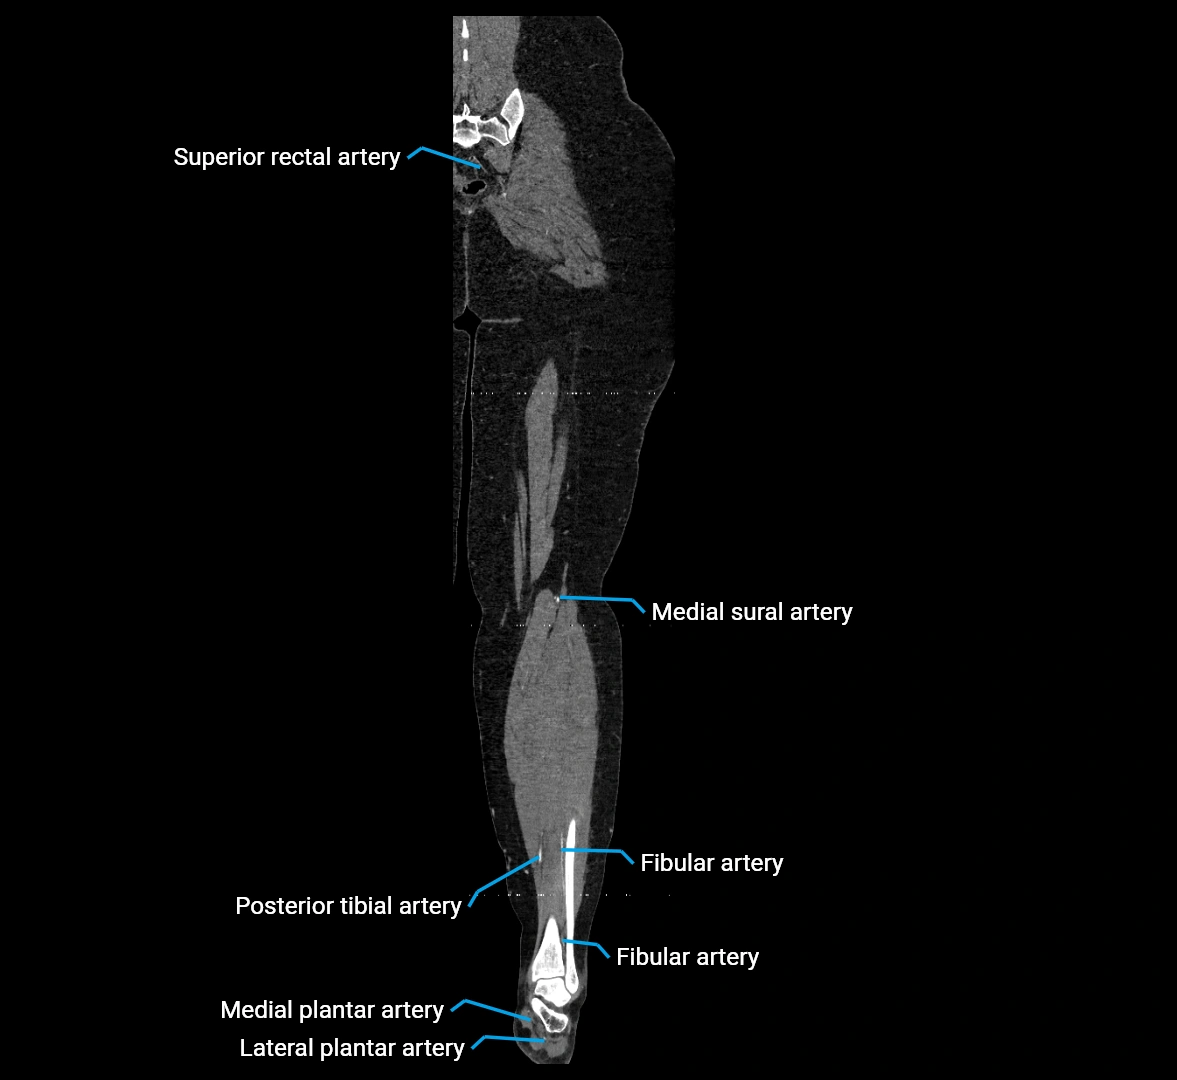

Contrast-enhanced CT (CTA):

• Gold standard for abdominal aortic imaging

• Provides excellent detail of lumen, wall, aneurysm, thrombus, and branch vessels

• Multiplanar and 3D reconstructions help in aneurysm measurement, stent graft planning, and dissection evaluation

• Detects acute rupture, traumatic injury, or occlusion with high sensitivity